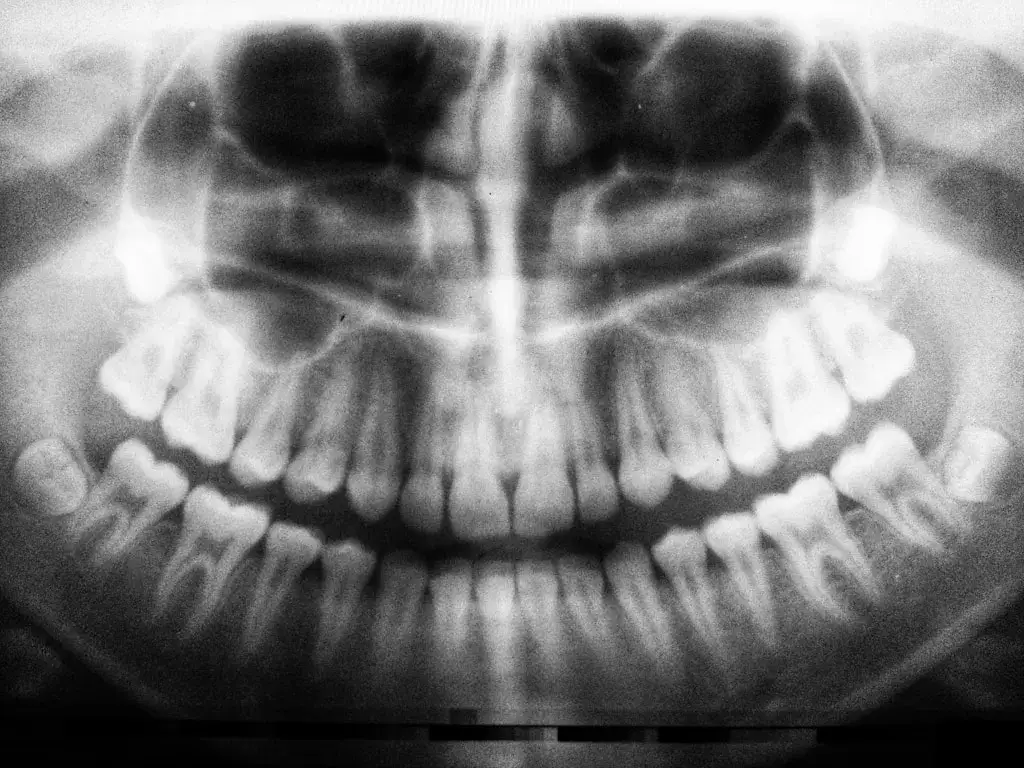

Obrazowanie radiologiczne stanowi nieodłączny element współczesnej diagnostyki stomatologicznej, umożliwiając precyzyjne rozpoznanie schorzeń oraz planowanie skutecznego leczenia. Wykorzystanie promieniowania rentgenowskiego pozwala na uzyskanie szczegółowych zdjęć zarówno pojedynczych zębów, jak i całych struktur szczękowo-twarzowych.